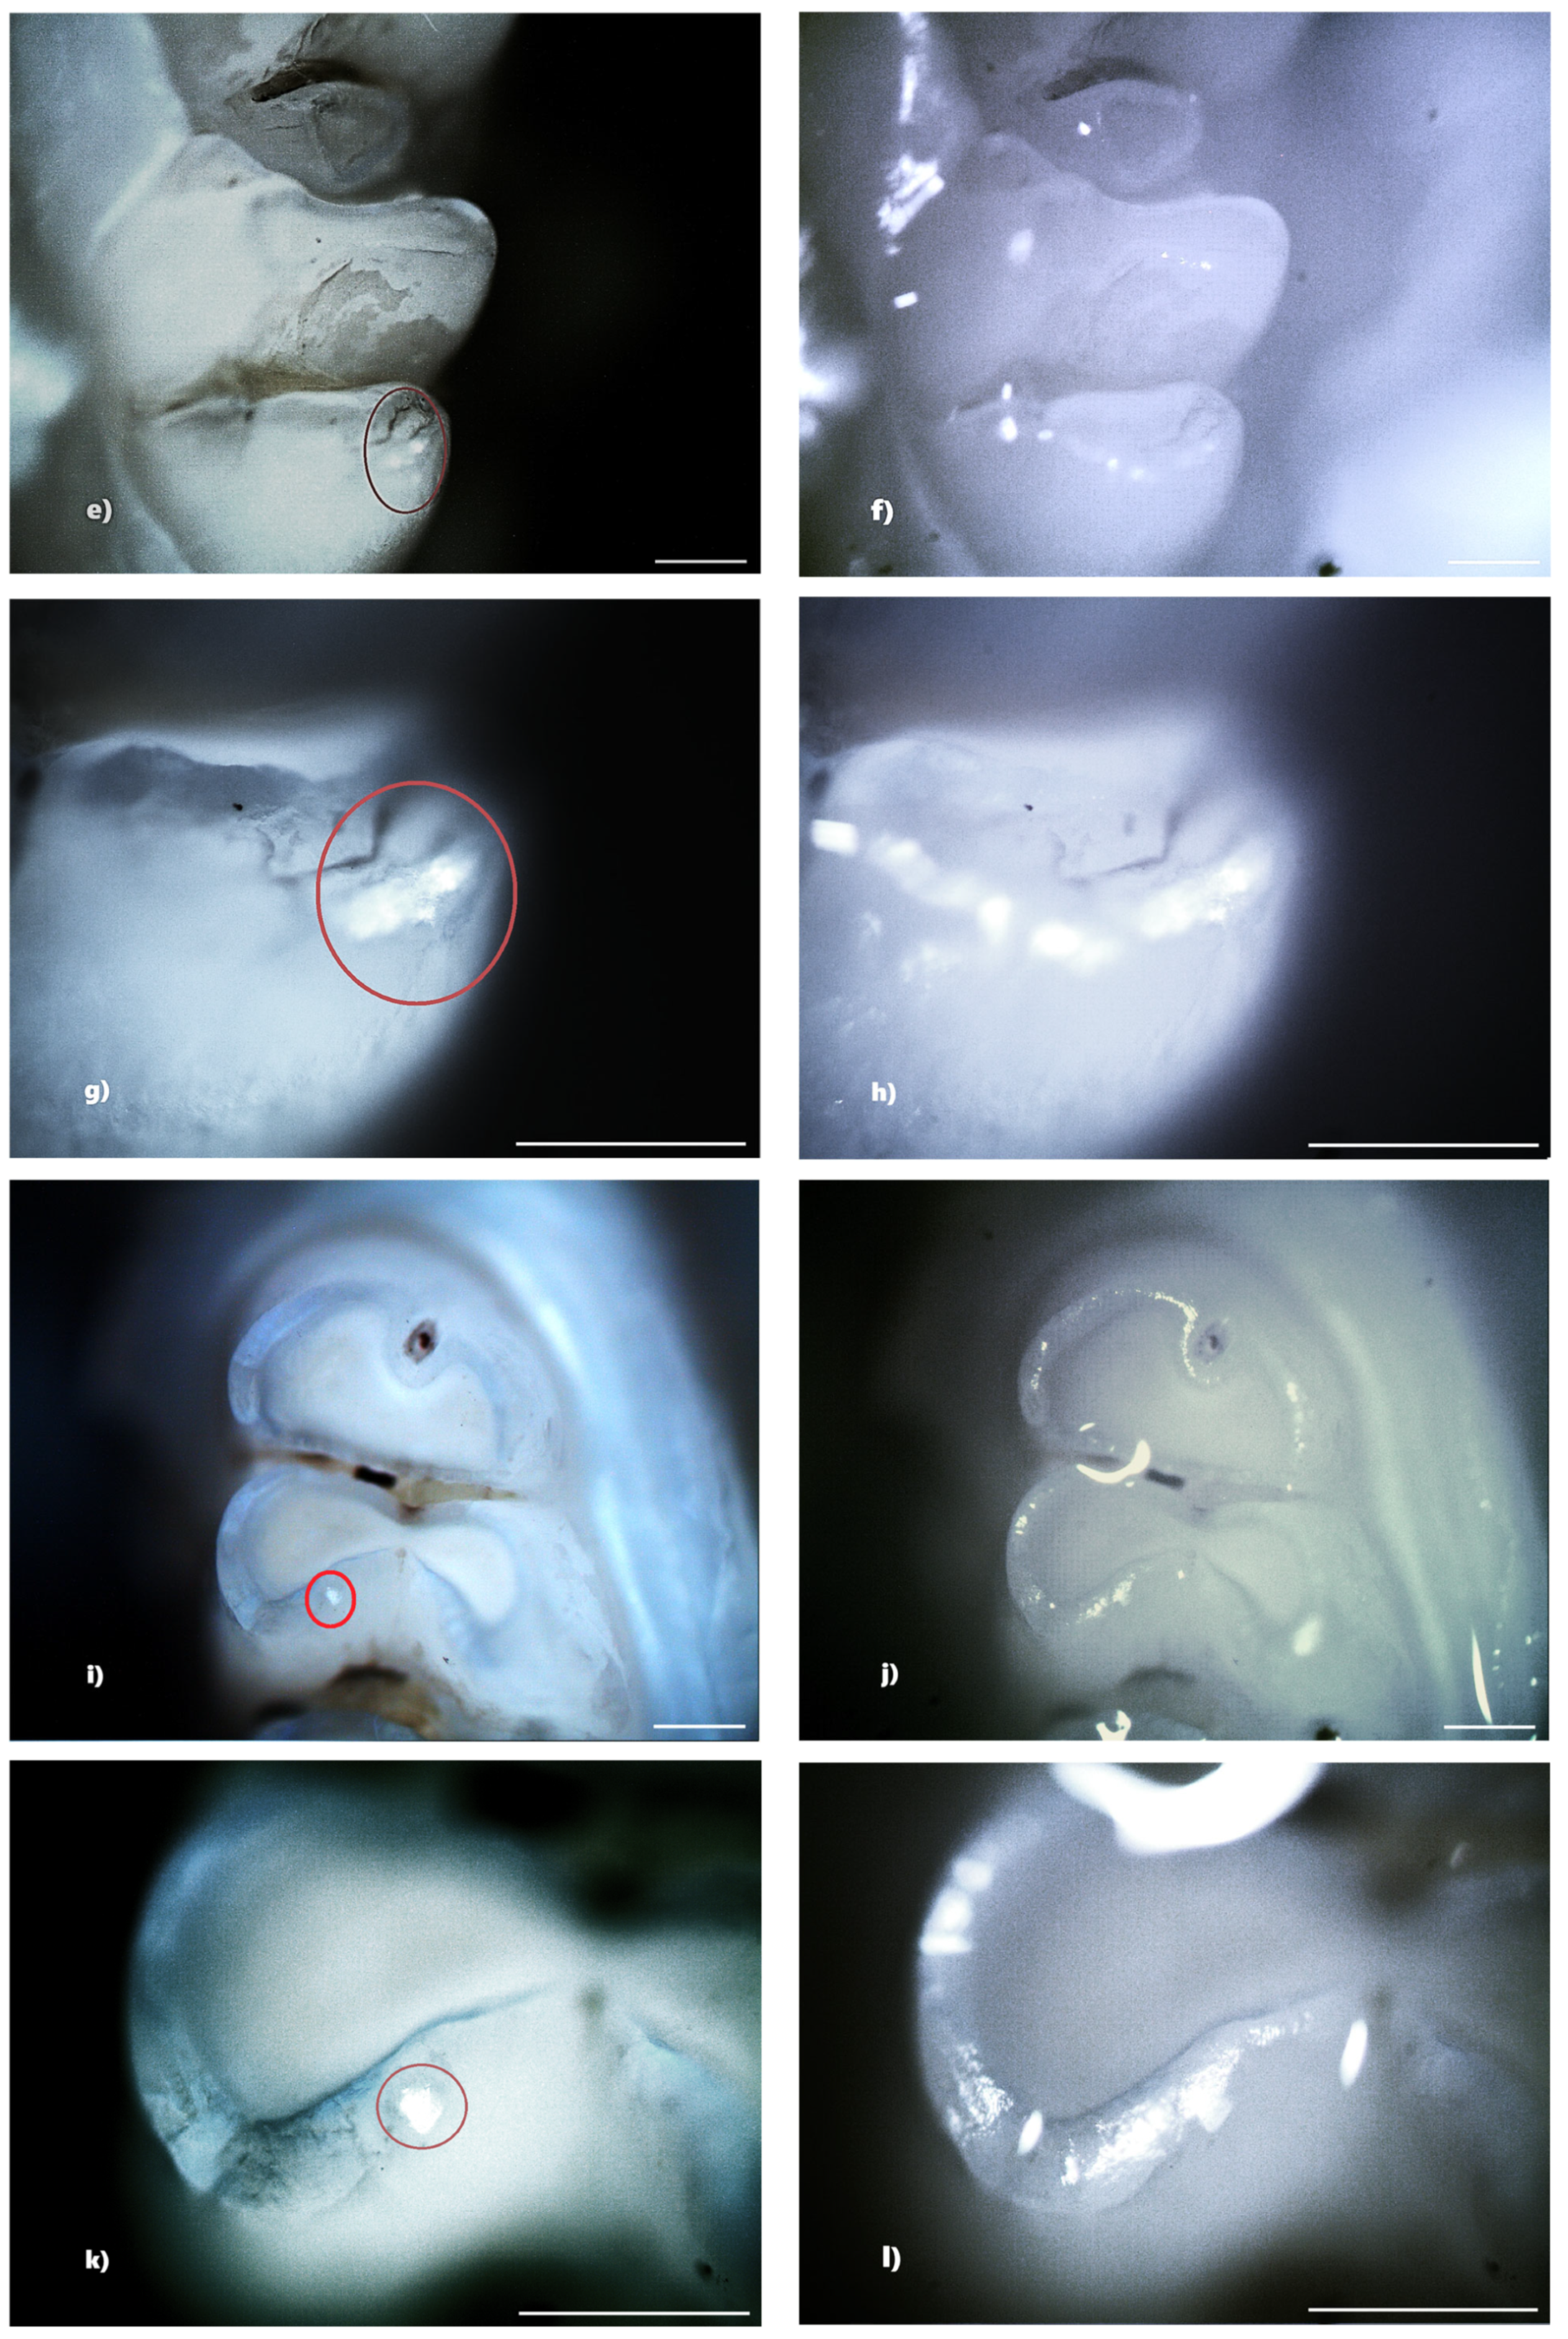

Figure 5. Hypoplasia on the palatal surface of a molar (a—PLM image, cross polarizers, 4× objective; b—BFM image, 4× objective) and on the distal surface of a molar (c—PLM image, cross polarizers, 4× objective; d—BFM image, 4× objective); demineralization on the occlusal surface of 2 molars (e,g—PLM image, cross polarizers, 4× objective; f,h—BFM image, 4× objective). Scale bar represents 500 μm.

In the standard dose amoxicillin group (50 mg/kg), 10 rats (66.67%) showed at least one clinical form of DDE. Of these, six rats showed hypoplasia, and three rats showed demineralization. One rat showed both clinical forms of DDE. Within this group, out of a total number of 240 teeth, 25 teeth (10.42%) showed at least one clinical form of DDE. Among them, 8 teeth (32%) were incisors and 17 teeth (68%) were molars, and as a clinical form of DDE, 16 teeth (64%) showed hypoplasia (five incisors and eleven molars) and 9 teeth (36%) showed demineralization (three incisors and six molars). Among the 25 teeth with DDE, 12 teeth (48%) presented lesions that were located on two surfaces, thus resulting in a total of 37 tooth surfaces with DDE (Figure 5).